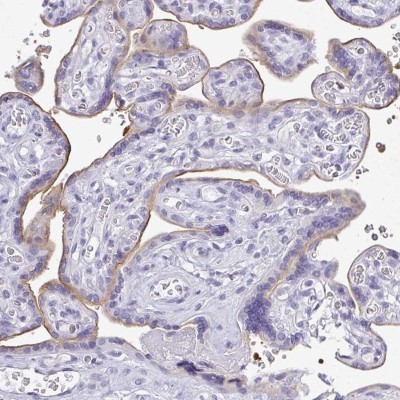

- Immunohistochemistry-Paraffin: LPPR3 Antibody [NBP2-33645] - Staining of human placenta shows moderate membranous positivity in trophoblastic cells.